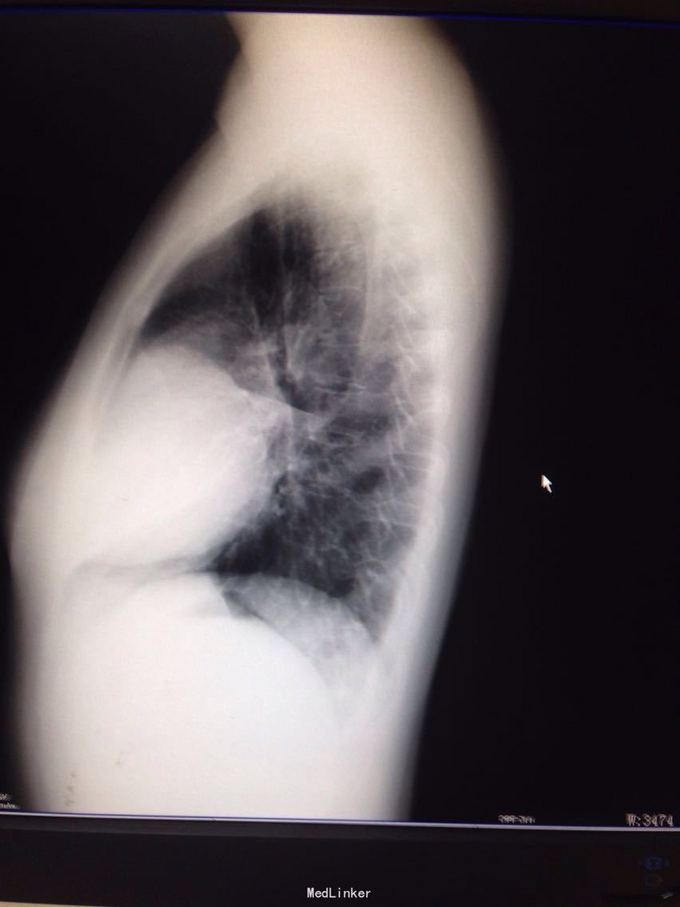

主诉:间歇性胸痛2年 病史:患者2年前无明显诱因出现胸痛,呈间歇性隐痛,约1至3月出现胸痛一次,每次持续约3-5天,近半年来感胸痛较前频发。并出现发作时胸闷、气促。至当地医院就诊,作胸部CT提示纵隔占位性病变。遂入我科手术治疗。

查体:双眼眼睑无明显下垂,结膜无充血,巩膜无黄染。双瞳孔等大等圆。气管居中,双侧胸廓无明显畸形,呼吸运动无受限。右侧中胸部叩诊浊音,左侧胸部叩诊清音,双肺呼吸音清,无啰音。 胸部CT提示右纵隔肿瘤。

诊断:右纵隔占位:畸胎瘤可能性大 处理:右侧前外侧切口第四肋进胸完成肿瘤切除,术中切开肿瘤见大量毛发形成,未见骨骼及牙齿形成